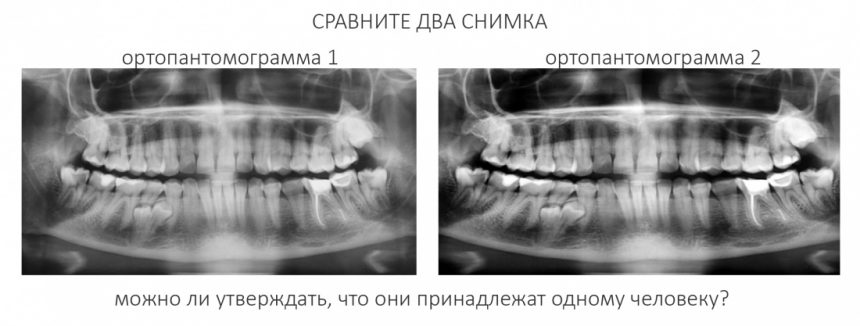

Современная медицинская наука — все ли средства хороши?